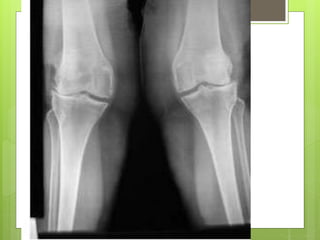

Radiographic changes

Kellgren and Lawrence classification

Radiographic changes Kellgren andLawrence classification

Clinical features  Mostlyoccurs in elderly  Mostly in major joints of the lower limb ( hip or knee)  Frequently bilaterally.  Pain is the earliest symptoms  It become intermittent initially and become constant over months and years.  Worsening during physical activites  Swelling of the joint is a late sign, due to inflammation.

Physical examination  Tendernessat the joint line  Crepitus on moving the joint  Irregular and enlarged looking joint due to formation of peripheral osteophytes  Deformity – Varus and valgus of the knee  Effusion – rare  Terminal limitation of the joint movement  Subluxation detected on ligament testing  Wasting of quadriceps femoris muscle.